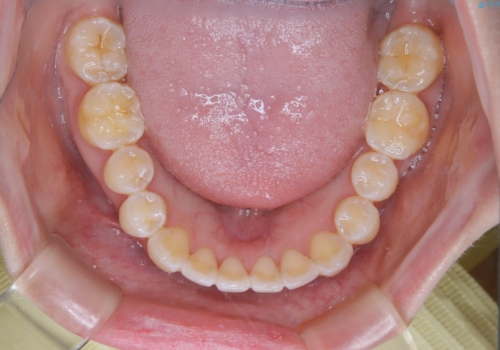

前歯で噛めない:オープンバイト(開咬)を非抜歯インビザラインで治療

- 上下の歯が噛んでいないことを気にしてご相談にいらした方です。

舌癖も認められたため、舌のトレーニングも併せて行い、矯正治療の効率化を図ると同時に後戻りのリスクを最小限に抑えるようにしました。

オープンバイトの方への治療は、通常抜歯を行いワイヤーによる矯正治療を行うことが多いですが、今回はインビザラインの特性を生かし、非抜歯にて綺麗な歯並びを作ることが出来ました。

舌癖がある方は、歯を内側から押し出す力が日常的に働くため、矯正治療後も歯と歯の隙間が開いてしまうなどの後戻りのリスクが高いことが知られています。舌の正しいポジショニングやお口周りの筋肉のトレーニングを行うことで後戻りのリスクを減らすことが可能です。